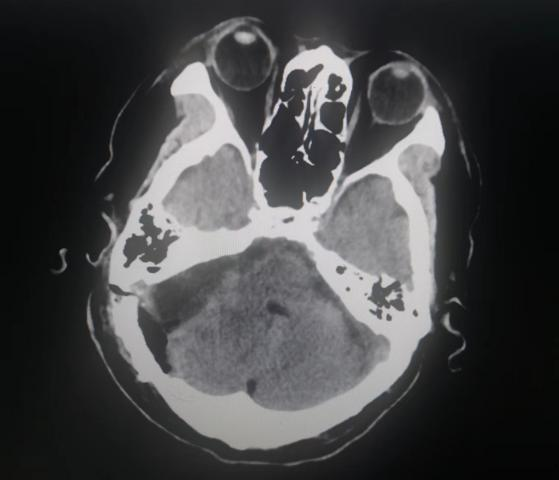

患者入院后,头颅MR检查后发现,小脑右侧长了巨大肿瘤,直径约6公分,患者家属收到不小的惊吓。患者4年前曾做过一次头颅核磁共振,当时肿瘤较小,考虑到患者已经88岁,家人还是决定保守观察,没想到如今,它已经长大到足足有一个土豆那么大,而且患者头晕较重,反复恶心、呕吐,卧床不起,因此必须进行手术,才能解决患者病症。